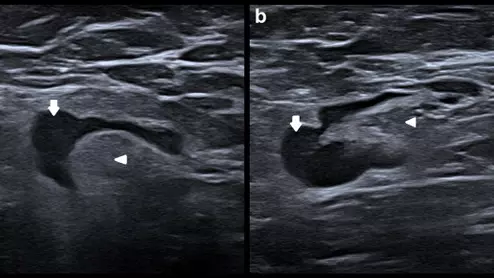

differentiating between malignant and vaccine-related lymphadenopathy